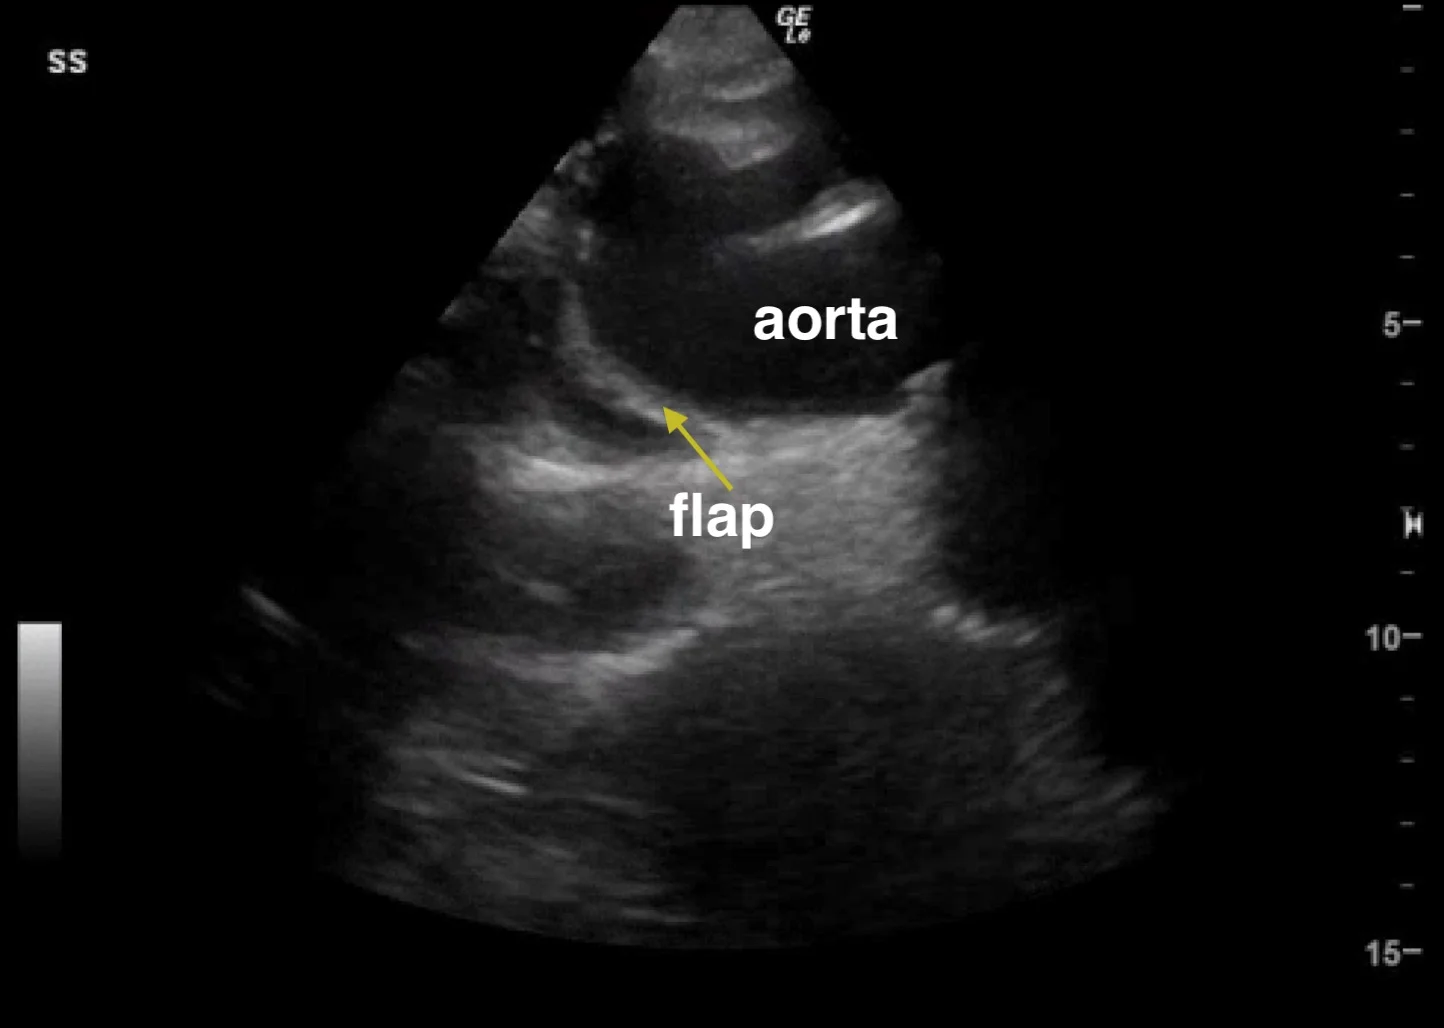

A 55 year-old male with history of hypertension presented to the ER with a chief complaint of "not feeling well" with leg pain and paresthesias. Upon further questioning, the patient admitted to waking up that morning with diaphoresis and pain in his upper back that had now migrated to his chest and upper abdomen. His exam was significant for bradycardia and diminished pulses in all four extremities. He had no murmur, no abdominal tenderness and no neurologic deficits. A bedside echo and ultrasound of the aorta was obtained and showed the following:

·     Presence of an intimal flap: while it can be challenging to identify, the finding of an intimal flap within the proximal aorta is pathognomonic for aortic dissection. A true flap will be seen to undulate within the aortic lumen and color flow can be used to demonstrate the presence of the false lumen. Beware of artifact mimicking a flap within the ascending aorta. Reverberation artifact from the aortic wall may appear as a line within the aortic root, but it will not have any fluttering or waving movements characteristic of a true dissection flap.

o  Also consider using the suprasternal notch view to obtain a coronal view of the aortic arch.

ssn.jpg